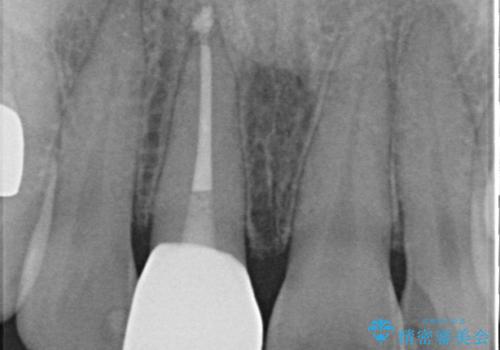

前歯に変色が起こる場合、神経組織の失活により引き起こる可能性が高いため、診察を行ったところ、根尖部の病変や叩いたときの痛みなどが認められました。

まずは根管治療を行い、痛みの消退を確認してからオールセラミッククラウンによる補綴治療を行うこととしました。